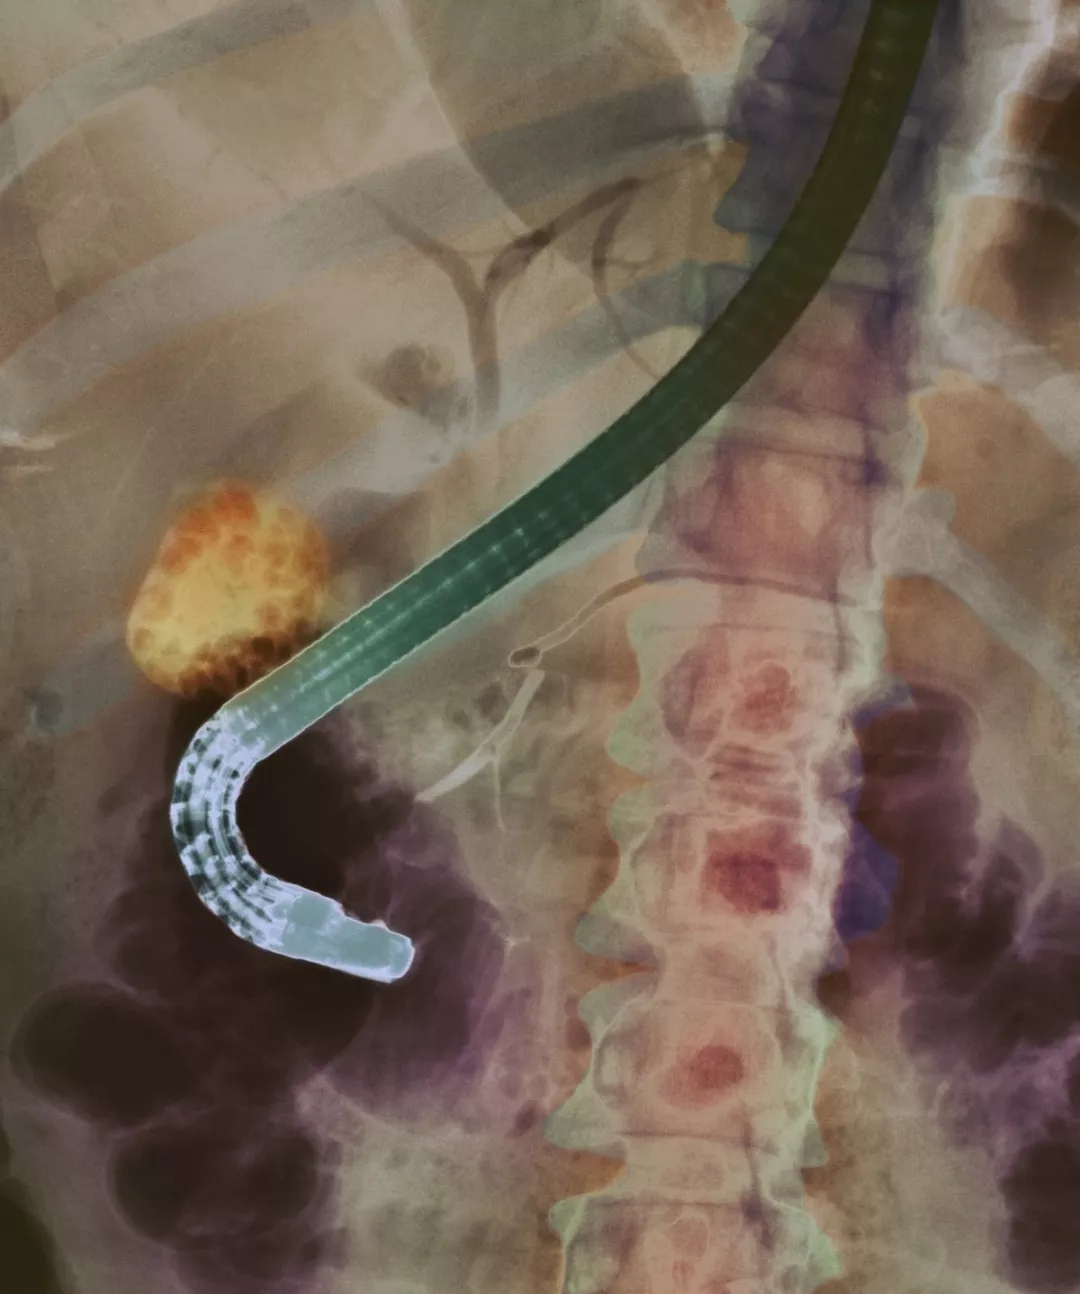

X光下病人胆囊中的结石(橘黄色),左边弯曲的的软管式设备即为内窥镜。图片来源:Science Source 在全球各地的医疗机构中,诊断和治疗胰腺和胆管等疾病时,都需要借助蛇形十二指肠镜这种工具。 但这些纤维光学元件,却存在一个显著的弊端:虽然可以通过口部将其插入小肠上半部分,并且重复使用,但却无法通过常规方式进行消毒。 通常情况下,它们都是经过手洗过后,再放入像洗碗机一样的机器中再次清洁的。在再次清洁过程中,还添加了专门的化学品,用来消灭微生物。即便每个过程都严格按照要求来清洁,这些设备上仍然可能留存细菌,并且病人可能会因此受感染。 实际上,在美国和欧洲的许多医疗机构中,都出现了十二指肠镜感染病人的情况,并且高达数百件病例。然而,根据最近的一项测试显示,有关监管机构严重地低估了其背后的风险。 更糟糕的是,这些设备甚至还可以造成耐药性感染的蔓延,而这种感染目前也几乎没有治愈方案。 部分担忧的医疗专家纷纷敦促美国食品和药物管理局(Food and Drug Administration,简称“FDA”)出台有关措施,强制要求制造商开发可以充分消毒的肠镜设备,或者杜绝使用市面上所有的十二指肠镜。 “这些感染数据非常恐怖,而且是不容辩驳的事实。因此,这些问题也需要立即得到解决。”北卡罗来纳大学(University of North Carolina)国家级感染管控项目的负责人威廉·拉塔拉(William A. Rutala)表示称。 在FDA的强制要求下,十二指肠镜的多个制造商也对其产品进行了测试。根据这些测试显示,即便是恰当清洁过后,仍然有5%的产品表面留存着可能会导致疾病的微生物,比如大肠杆菌。 而在测试之前,根据FDA的预估,清洁过后仍然会留存细菌的可能性不高于千分之五。 拉塔拉的同事、该项目的医疗主任大卫·韦伯(David Jay Weber)博士称,“这个结果实在是太令人震惊了。”他强烈建议FDA,必须要设定一个截止日期,让这些制造商在这个日期之前解决这个问题。 “如果飞行员告诉你,‘顺便说一下,发动机失灵的可能性只有5%’,那你还愿意上这架飞机吗?”韦伯说,“如果制造商告诉你,‘我们的车上都是配备了安全气囊的,但安全气囊失灵无法弹出的可能性有5%’,那你又敢坐这个车吗?” FDA设备和放射线健康中心主任杰夫·舒仁(Jeff Shuren)建议说,FDA应该采取额外的监管行为。“绝对有必要采取有关改善措施。”他在今年四月份发表的一份声明中表示称。然而,截至目前,FDA仍然没有采取任何行动。 隐藏的瑕疵

十二指肠镜的一端,它与一条长长的可屈性软管相连接。因构造的复杂性,导致对其的清洗和消毒异常复杂。图片来源:Food and Drug Administration/Associated Press 十二指肠镜是一条长长的具有高延展性的软管,在软管的其中一端,装配有纤维光学摄像头。整条软管都可以从病人口腔直插进胃部,然后插入小肠的上半部分,也被称作十二指肠。 这个过程,医学上被称作“内窥镜逆行胰胆管造影(ERCP)”,主要是用来诊断和治疗胰腺、胆管和胆囊等疾病,比如可能会致命的黄疸病、肿瘤、胆道梗阻以及结石等。在美国,每年有超过50万人都接受了ERCP诊断。 而ERCP诊断的替代方案,则是开放手术,即需要切开表皮的手术。当然,美国明尼苏达州罗切斯特梅奥医学中心(Mayo Clinic)胃肠病学家布雷特·彼得森(Bret Petersen)博士称,手术必然存在一定的风险。“如今,几乎没有人还会选择开放手术来摘除胆结石了。” 然而,彼得森也承认,如今无法完全清洁肠镜的事实,也成了肠镜的一个“致命弱点”。虽然有很多医学仪器都可以用高温来消毒,但十二指肠镜却无法通过高温消毒。 就十二指肠镜而言,目前很难用手清洗狭窄的软管内部,而和其它的内窥镜不同的是,十二指肠镜的顶端还设计有一个可移动式升降结构,借助于这个结构,也可以更好地调整手术器械的具体位置。 然而,也正是因为这个结构,设备的微小裂缝成了身体体液以及细菌的滋生繁衍地,从而让更个清洁过程变得更复杂。 在美国,主要的十二指肠镜制造商包括奥林巴斯医疗系统公司(Olympus Medical Systems Corp.)、宾得公司(Pentax)以及美国富士胶片医疗系统公司(Fujifilm Medical Systems USA)。其中,奥林巴斯的市场份额最大。 在众多医疗机构频频爆出十二指肠镜感染问题之前,FDA从来没有要求查阅这些制造商有关如何清洁设备的数据和内容。 就FDA的现行规定而言,如果市场上新出现的医疗设备被认为和现有设备“非常相似”的话,这些新设备就无需再进行安全和效能测试。而确保新设备能够恰当工作的重任,也全部落在了制造商的肩上。 这些制造商声称,只要医疗健康机构根据设备说明书对十二指肠镜进行清洁和消毒的,那这些设备对病人而言就是安全的。根据说明书,这一系列清洁和消毒过程非常复杂,整个过程超过上百个步骤,其中包括在清洁后通过肉眼检查“设备上有无可见的尘土或碎片”。 说明书还提到,每年都应该把这些设备送回至制造商指定地点,进行相应的维修保养。 然而,自2012年以来,美国和欧洲出现了上百例因十二指肠镜清洁不当而受感染的案例。其中,很多病例都是因感染碳青霉烯类抗生素耐药肠杆菌科细菌(carbapenem-resistant Enterobacteriaceae,简称“CRE”)所致。对于CRE细菌,药效非常强劲的抗生素也无可奈何。一旦受CRE细菌所感染,起码有50%的人都可能会性命不保。 2012年至2014年期间,西雅图有超过30名病人都因十二指肠镜而感染CRE细菌,其中11人死亡,还有多名病人出现了病重等情况。2013年,伊利诺斯州的帕克里奇也出现了数十位感染CRE细菌的病例。 2015年,加州大学洛杉矶分校医疗中心附属里根医疗中心( Ronald Reagan UCLA Medical Center)也出现了因十二指肠镜使用不当而导致病人感染CRE细菌的案例,其中2名病人死亡,5名病人病重。